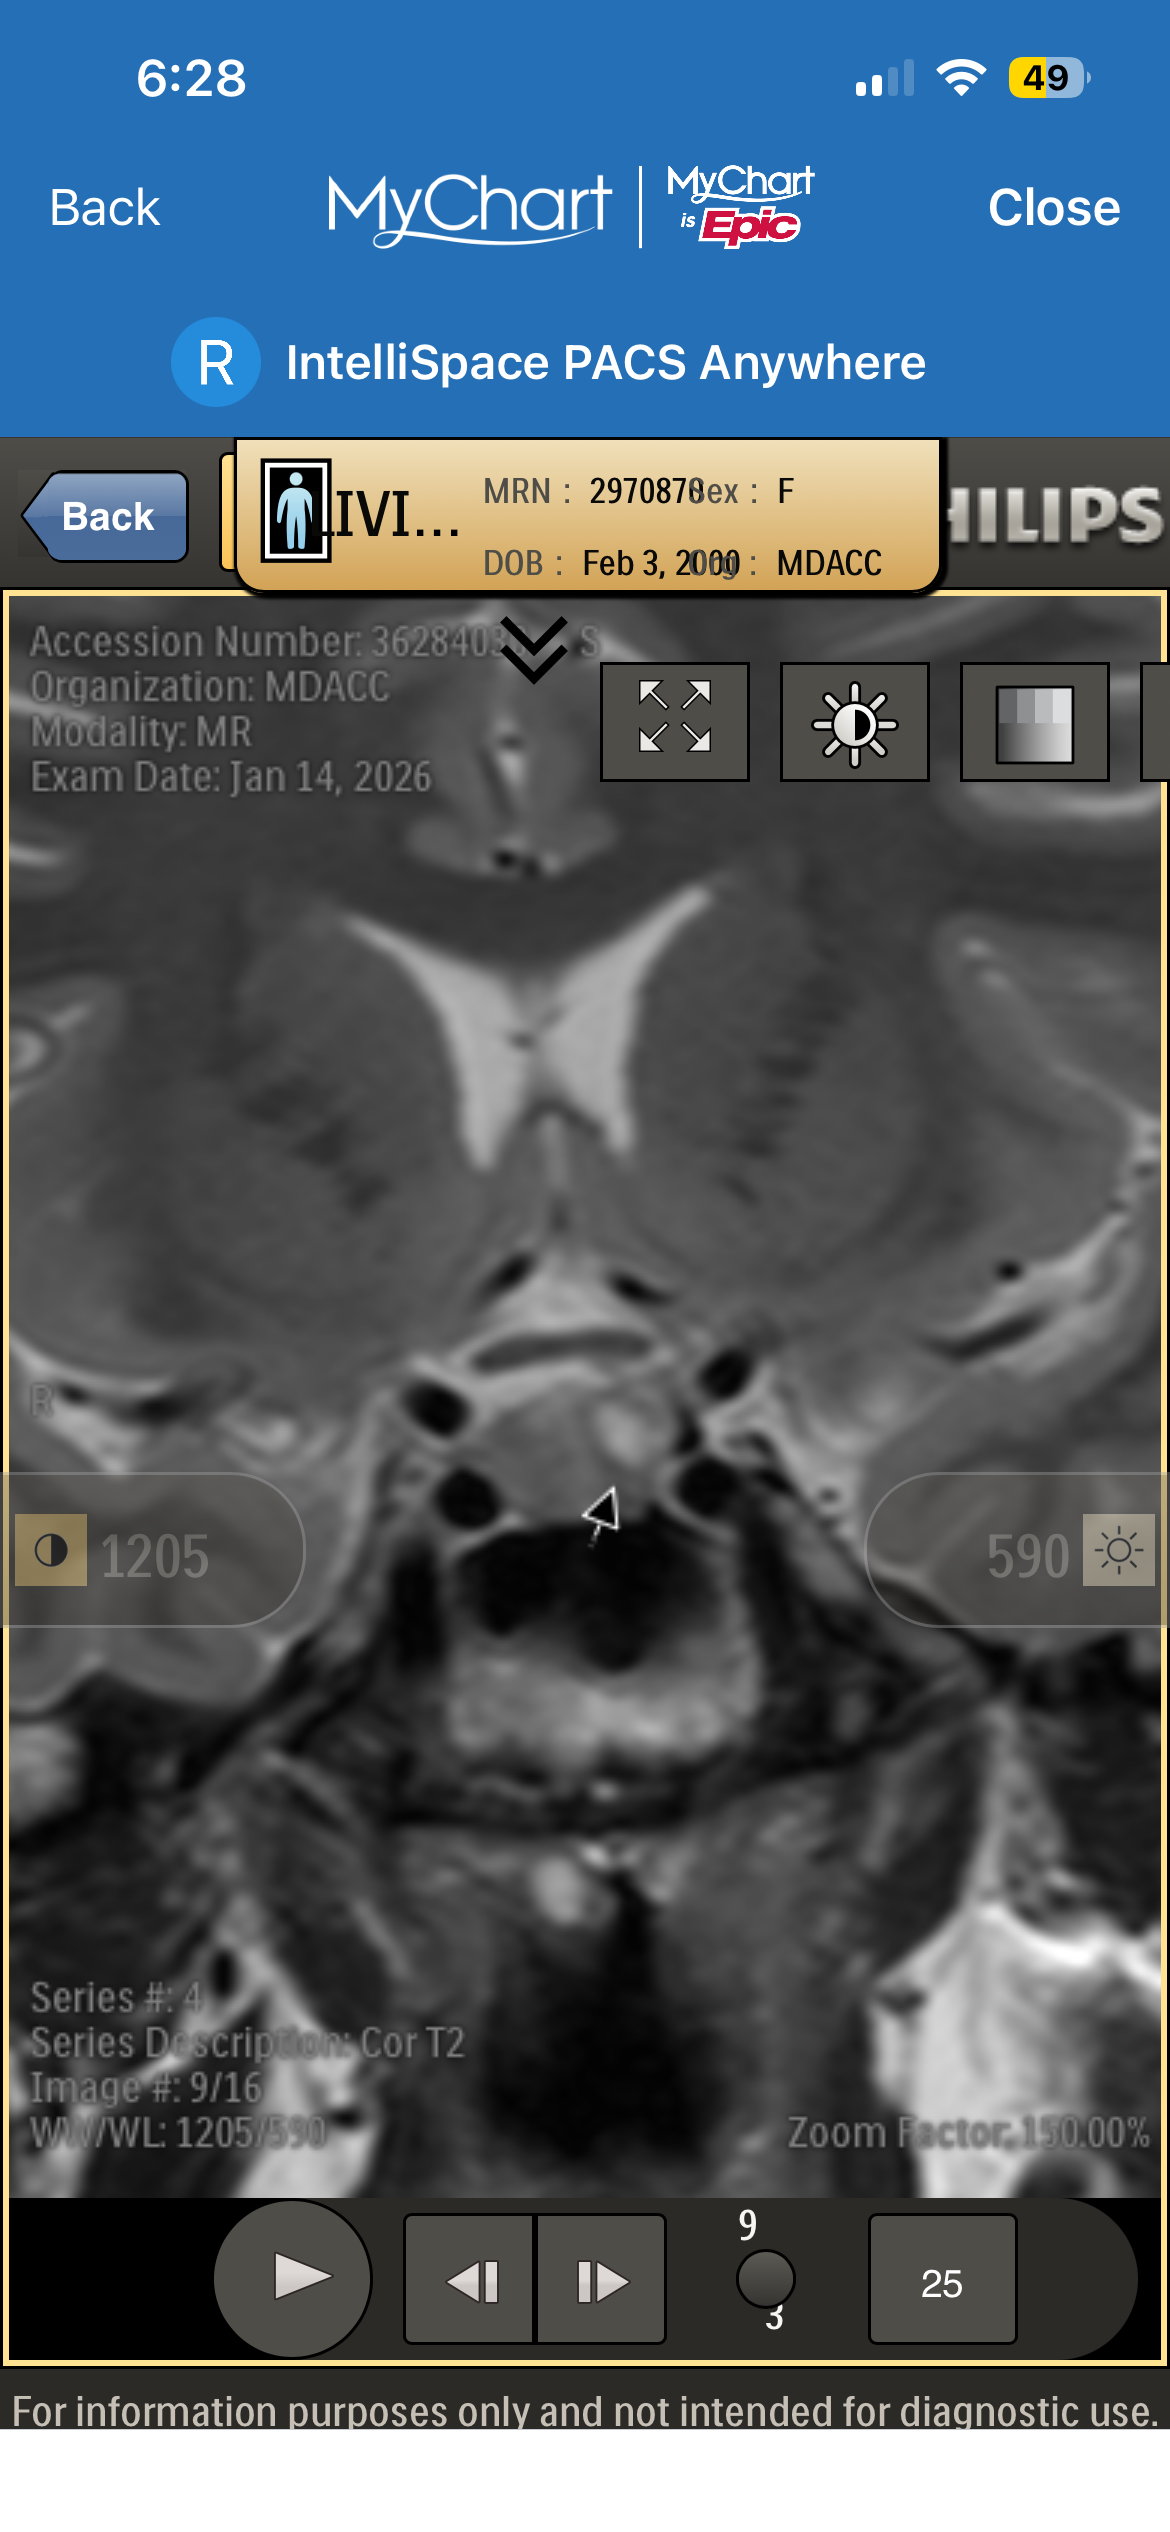

Recently, I was diagnosed with a pituitary brain tumor. Since then, my life—and my family’s—has changed in ways we couldn’t have prepared for. Between medical appointments, testing, treatment planning, and travel for specialized care, the financial and emotional weight has become heavy very quickly.